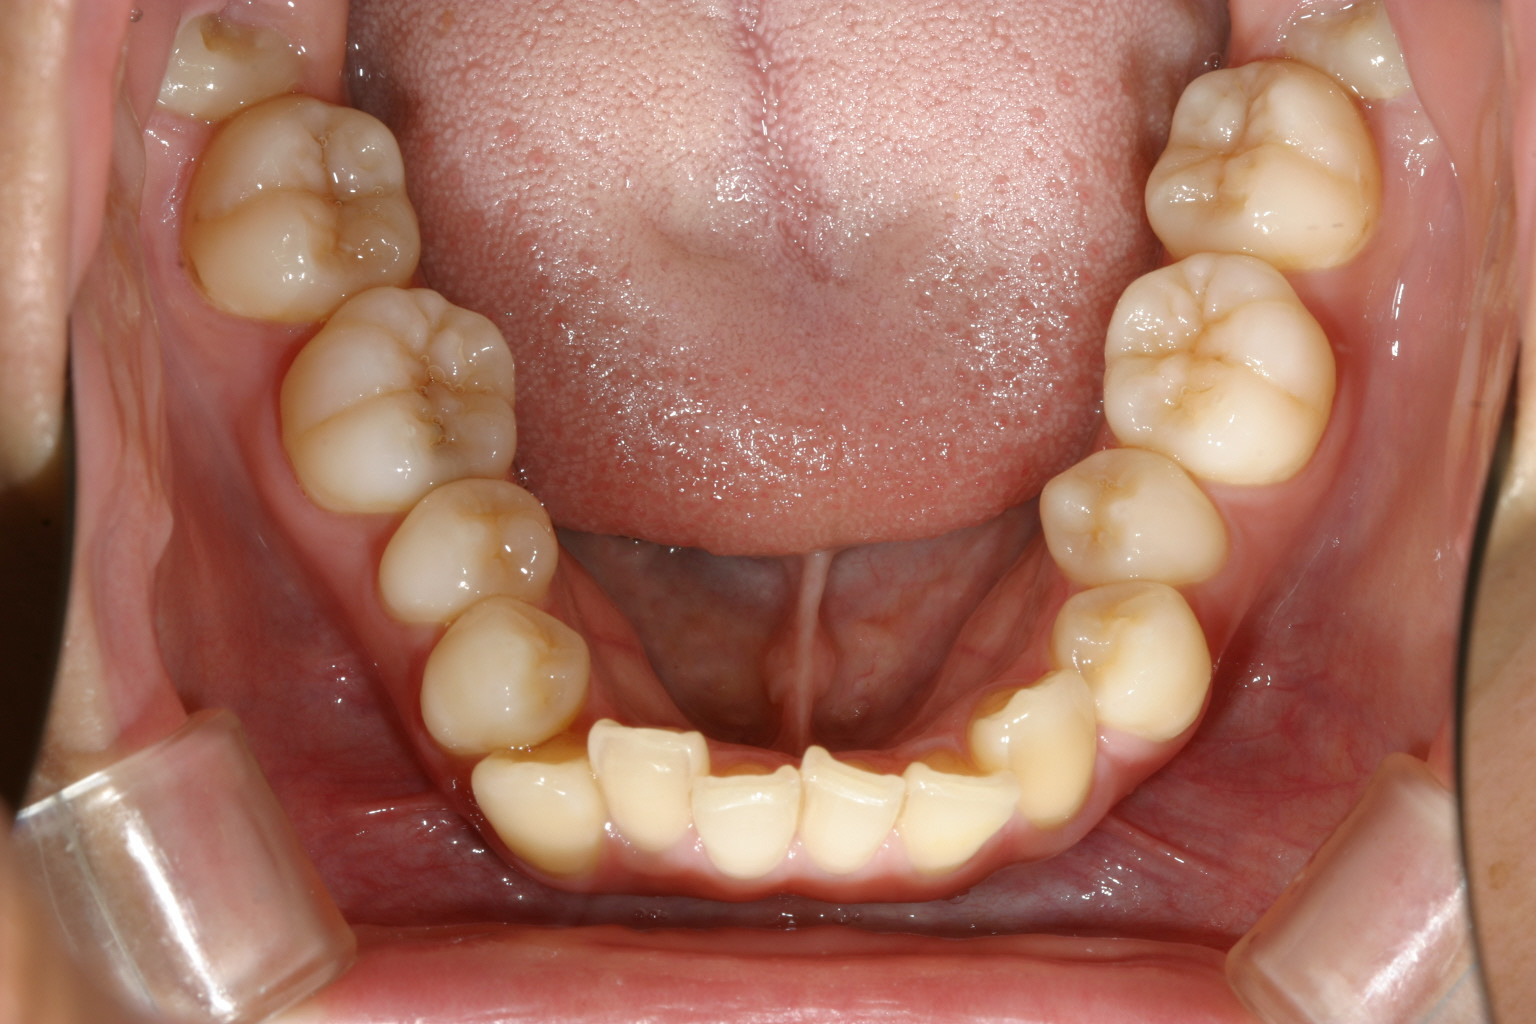

下顎にもガタガタが見受けられます。奥歯が全体的に内方へ倒れ歯列がV字形になってる為前歯がガタガタしているのです。

少し出っ歯観があり、咬み合わせがが深いです。